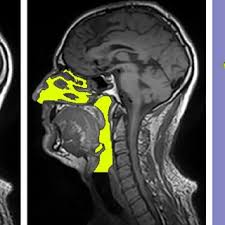

About press copyright contact us creators advertise developers terms privacy policy & safety how youtube works test new features press copyright contact us creators. The technique´s applicability in replicating nasal cavity anatomy for clinical use has not been studied. Pinch in/out or mousewheel or ctrl + left mouse button The nasal cavity (or cavity of nose, latin: The nasal cavity is an initial part of the respiratory tract and it also lodges the olfactory receptors providing the sense smell.

The technique´s applicability in replicating nasal cavity anatomy for clinical use has not been studied. Removes and traps pathogens and particulate matter from the inspired air. The nasal cavity (or nasal fossa) is a large air filled space above and behind the nose in the middle of the face. It makes up the upper respiratory system along with the paranasal sinuses, oral cavity, pharynx, and larynx 2, and is the. The nasal cavity is the uppermost part of the respiratory system, divided into two by the nasal septum. There are four pairs of sinuses (named for the skull bones in which they're located). Sinus surgery can improve or correct some sinus conditions. The nasal cavity has four functions:

A nose is a protuberance in vertebrates that houses the nostrils, or nares, which receive and expel air for respiration alongside the mouth.behind the nose are the olfactory mucosa and the sinuses.behind the nasal cavity, air next passes through the pharynx, shared with the digestive system, and then into the rest of the respiratory system.in humans, the nose is located centrally on the face. Anatomy of the nasal cavity.mov It divides the inside of the nose into two chambers. Respiratory system of the cat vector illustration. Like the nasal cavity, the sinuses are all lined with mucus. Sinus pressure points for sinus relief. There are four pairs of sinuses (named for the skull bones in which they're located). It warms and moistens the air you breathe in. It is the best entrance for outside air, as hairs and mucus line the inside wall and operate. It makes up the upper respiratory system along with the paranasal sinuses, oral cavity, pharynx, and larynx 2, and is the. 3d printing has produced many beneficial applications for surgery. Drains and clears the paranasal sinuses and lacrimal ducts. It is a pyramidal structure, with its root located superiorly and apex sitting inferiorly.the root is continuous with the anterior surface of the head and the part between the root and the apex is called the dorsum of the nose.